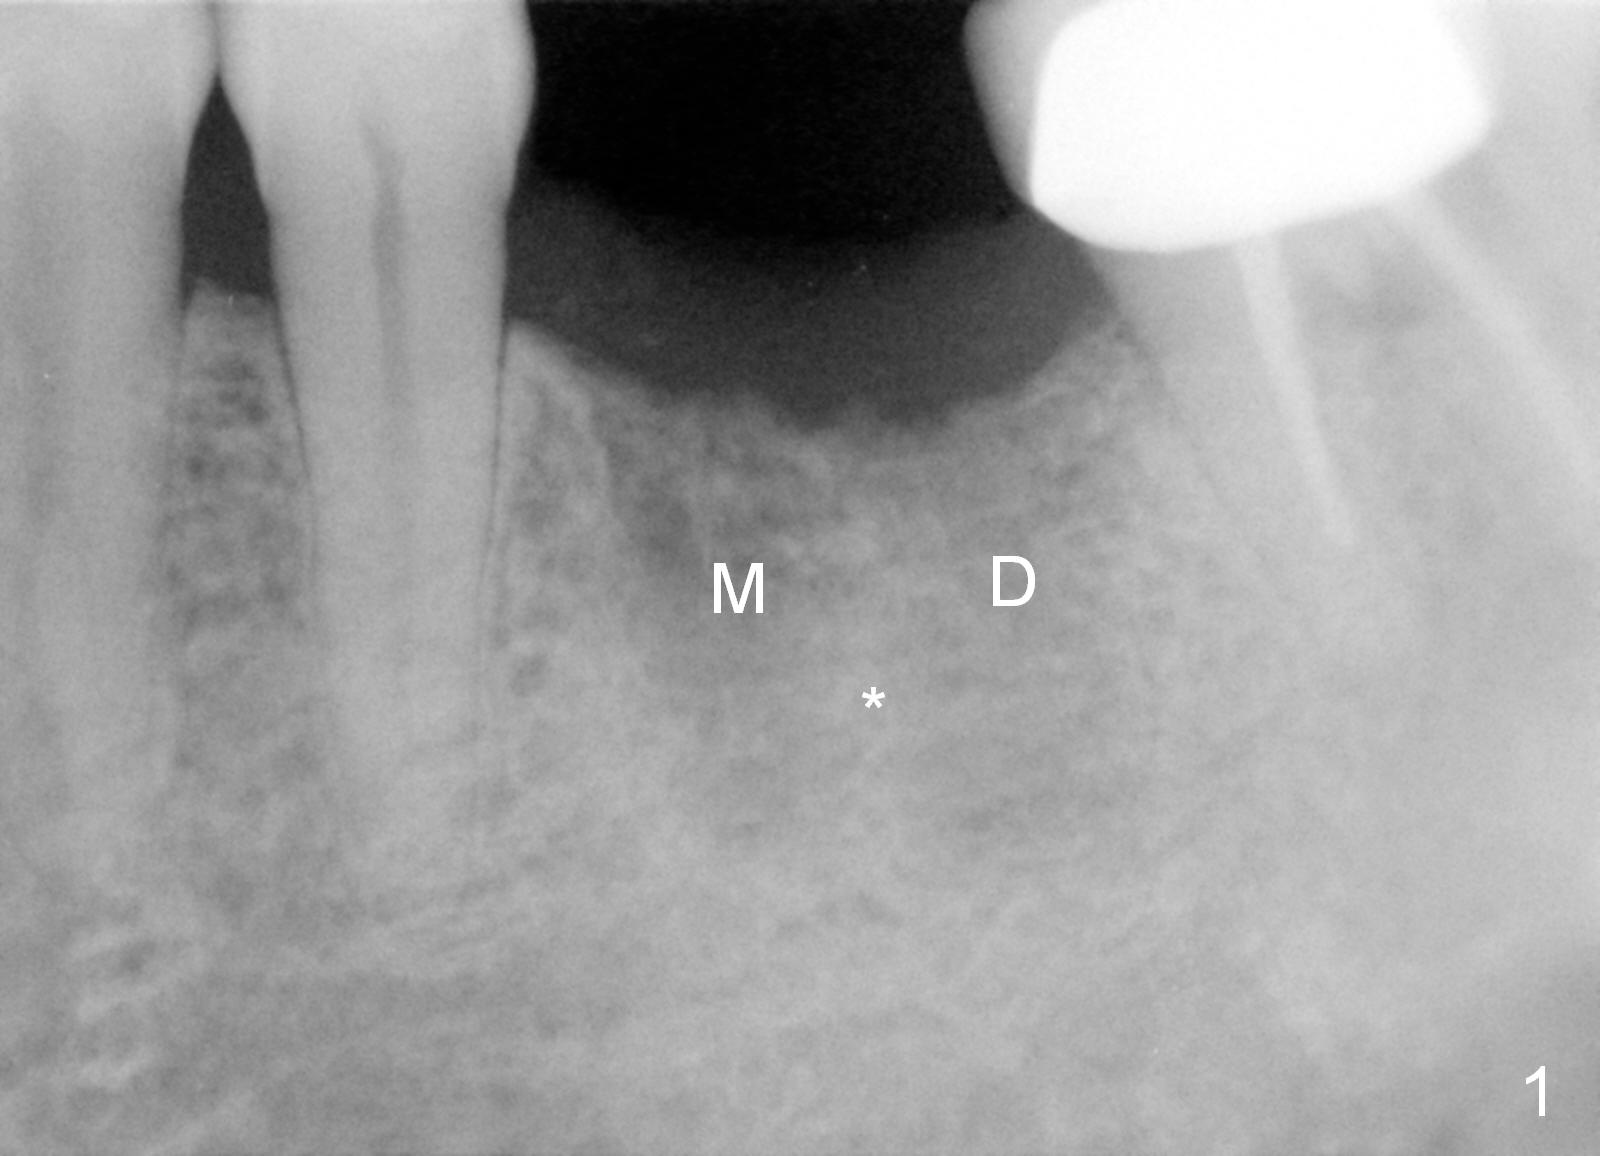

A 68-year-old man had the tooth #19 extracted more than 6 months ago (Fig.1). When his wife has had an immediate implant placed, he decides to have his implant placed. After incision, use the 5 mm implant positioner to check the width of the crestal bone. If it is less than 6 mm, the implant length will be most likely 14 mm. Clinical exam has revealed moderate ridge atrophy. Anyway, the initial osteotomy is 12 mm. It should pass the apices of the mesial (M) and distal (D) sockets (Fig.2 ^) in the middle of the septum (as compared to Fig.1 S). If there is enough safety margin, the osteotomy depth will be set at 14 mm (Fig.3 (red dashed line: the superior border of the Inferior Alveolar Canal)). There is no indication for intraop localized use of antibiotic.